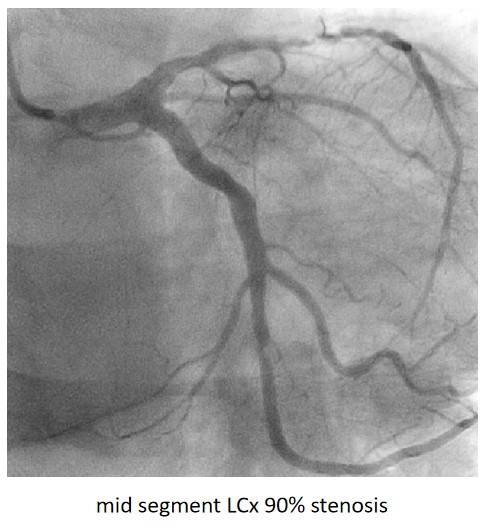

Urgent coronary angiography showed smooth LMCA with severe 3-vessel involvement. There was diffuse LAD lesion with critical stenosis at proximal-to-mid segment. Mid-segment of LCx was 90% stenosed while RCA was heavily calcified with critical stenosis at its mid segment. Our strategy will be complete revascularisation by employing DCB-only strategy.

Complete revascularisation was achieved with 2-staged procedures. Up-front plaque modification with rotational atherectomy/IVL with IVUS was planned but limited by patient¡¯s cost constraint. Vascular access obtained with transradial puncture with 6 Fr sheath. Guiding catheter (GC) Judkins Right 4.0 (Cordis, USA) 6 Fr was used to engage right coronary ostium. Runthrough Floppy (Terumo, Japan) wire was wired down RCA. Pre-dilatation balloons were unable to cross the heavily calcified mRCA lesion. Next, GC was changed to Amplatz Left 1.0 (Cordis, USA) for better support and proceeded for further lesion preparation with cutting balloon Wolverine (Boston Scientific, USA) 3.5 x 10 mm and DCB Prevail (Medtronic, USA) 3.0 x 20 mm was deployed. We scheduled him for staged PCI to the left coronaries in 2 weeks time via transradial approach with 6 Fr sheath. GC XB LAD 3.5 (Cordis, USA) 6 Fr was used to engage left coronary ostium. Runthrough Floppy was wired down LCx. Mid-distal LCx was prepared with Pantera Pro (Biotronik, Germany) 2.5 x 15 mm and DCB Pantera Lux (Biotronik ,Germany) 3.0 x 15 mm was deployed. Finally, we wired down LAD with Runthrough Floppy. Mid-distal LAD lesion was prepared with Pantera Pro 2.5 x 15 mm and DCB Pantera Lux 3.0 x 30 mm was deployed. Proximal LAD lesion, which was calcified, was further prepared with Wolverine 2.5 x 10 mm before DCB Pantera Lux 3.5 x 30 mm was deployed. Final post-PCI results were acceptable, achieving complete revascularisation for him.